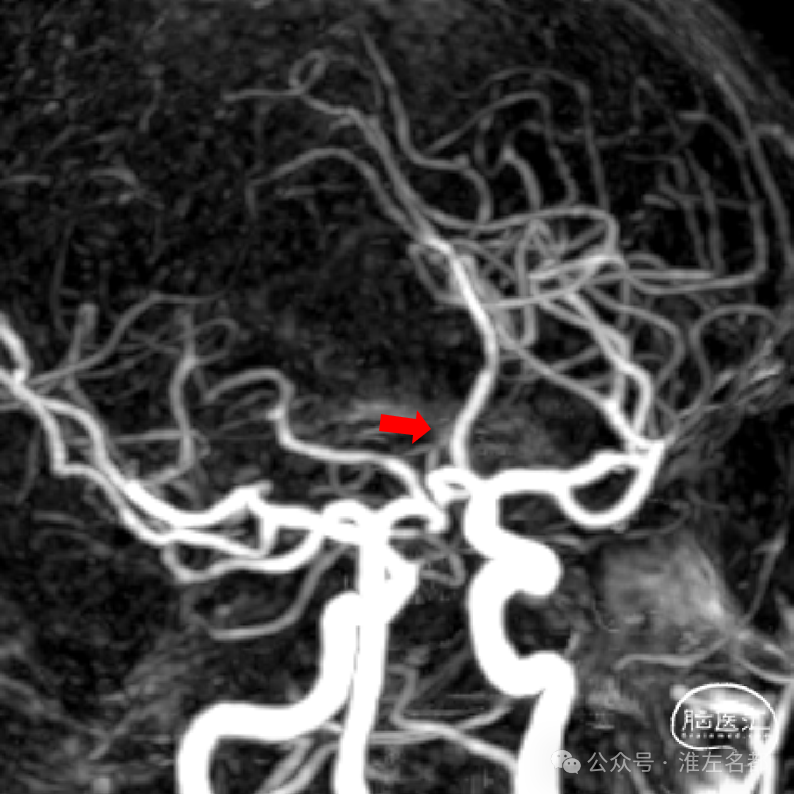

微导管通过闭塞位置,造影证实位于真腔。

经微导管释放取栓支架(S AB 4*20mm)后造影,前向血流恢复,局部狭窄(红箭)。

回收取栓支架后造影:闭塞再通,右侧A2局部轻微狭窄,但A3-4交界处可见造影剂渗出,提示出血。

予以降压等处理,约5分钟后造影提示出血已经停止。

取出少量血栓

术中DSA平板CT示:前纵裂旁少量蛛网膜下腔出血。